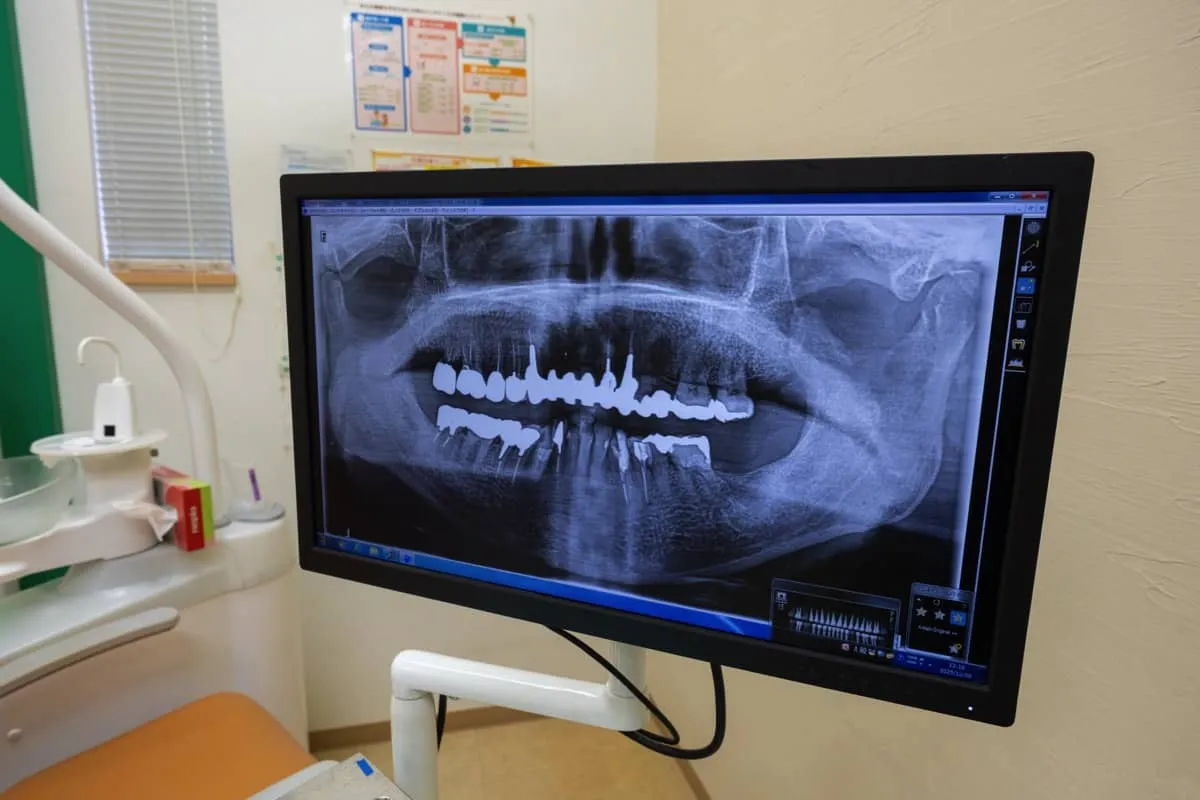

一見何の異常も感じられないように見えても、虫歯は静かに進行し、知らないうちに歯の内部を蝕んでいきます。冷たいものがしみたり、過去に治療した歯がなんとなく気になったり、そんな微細な違和感が虫歯のサインであることも少なくありません。初期のうちに発見できれば歯を削る範囲を抑えられ、治療の負担も格段に軽くなります。そのため、痛みや不安に配慮しながら安心して受けられる丁寧な治療を港区で行っております。

カウンセリングで症状を細かく把握

症状が進んでからではなく、違和感を覚えた時点での受診が歯科治療においてとても重要な意味を持ちます。だからこそ、カウンセリングにはしっかり時間をとり、痛みの有無や過去の治療歴、普段のケア方法まで丁寧に伺います。そのうえでお口の状態を正確に把握し、できるだけ歯を削らない処置を基本に据えながら的確な治療計画を組み立てていきます。虫歯は、放置してしまうと結果として大きな治療が必要となることもあるため、早い段階で原因にアプローチし、機能性や見た目をできる限り損なわずに回復できるよう港区で尽力いたします。